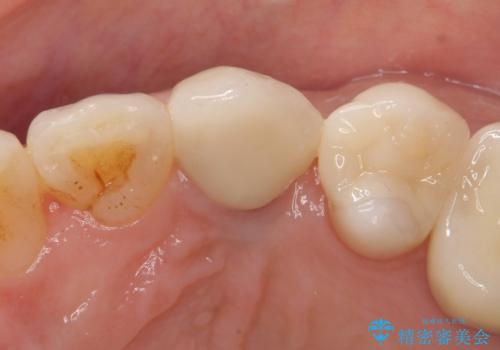

左:虫歯を除去したところ。遠心が歯ぐきより深い状態です。中:そのままかぶせようとすると、遠心が歯ぐきが腫れやすい状態です。右:エクストリュージョンをしたことで、遠心の歯ぐきの腫れが収まっていることがわかります。

エクストリュージョンをしたことで、いくら歯磨きを頑張ってもどうしても腫れてしまう歯肉に対して、歯周囲組織の位置関係を変えることで根本的に解決しました。